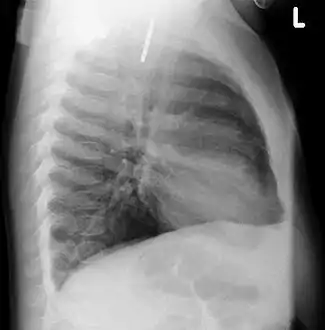

- A coin seen on lateral CXR in the esophagus

- Lateral X ray showing a 9mm battery in the intestines